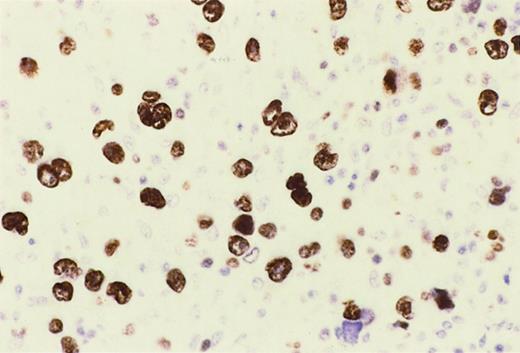

Reed-Sternberg cells of HIV-HL express MUM1.

In a lymph node involved by lymphocyte depletion HIV-HL (case 16, Table4), MUM1 is expressed by a large number of tumor cells corresponding to RS cells and their variants. The staining is nuclear and intense. Immunoperoxidase, hematoxylin counterstain. Original magnification, × 250.

HIV-HL